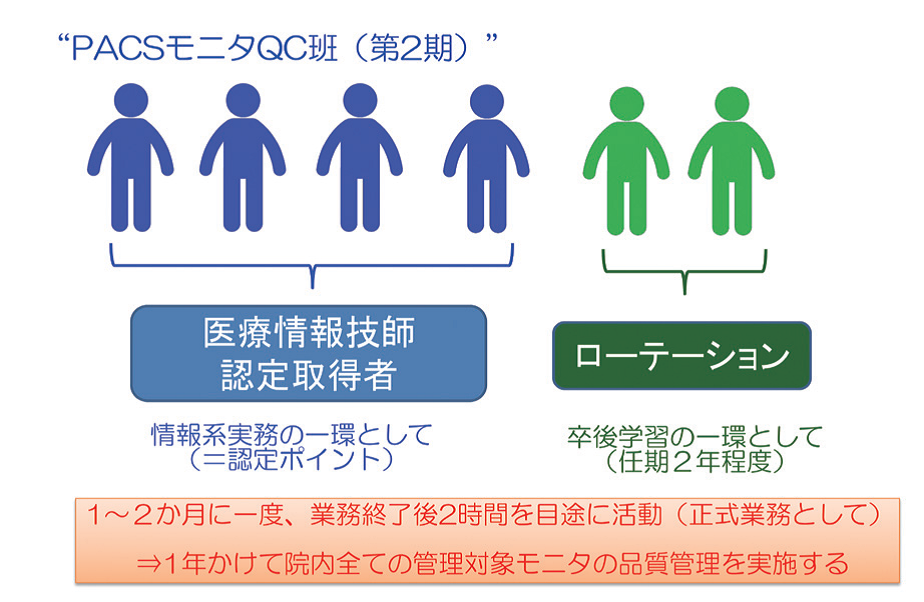

実施には部門全体で取り組み、過度な負担のない参加型としている(図2)。QC班は6名で、1、2カ月に一度、業務終了後2時間を目処に行い、1年かけて院内全台に実施する体制を構築した。